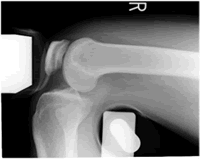

前十字靭帯断裂のときは、脛骨が異常に前方に引き出されます。lachmanテストで大まかな診断がつきますが、損傷の程度を知るために単純XP撮影、CTスキャン、関節造影、MRIなどが実施され、MRIがとても有効です。動揺関節の立証には、ストレスXP撮影が必要です。

𦙾骨を前方に引き出し、ストレスをかけてXP撮影を行います。断裂があるときは、脛骨が前方に引き出されて写ります。後遺障害診断書には、およその計測値ではありますが、「○mmの前方引き出しを認める」と記載をお願いしなければなりません。